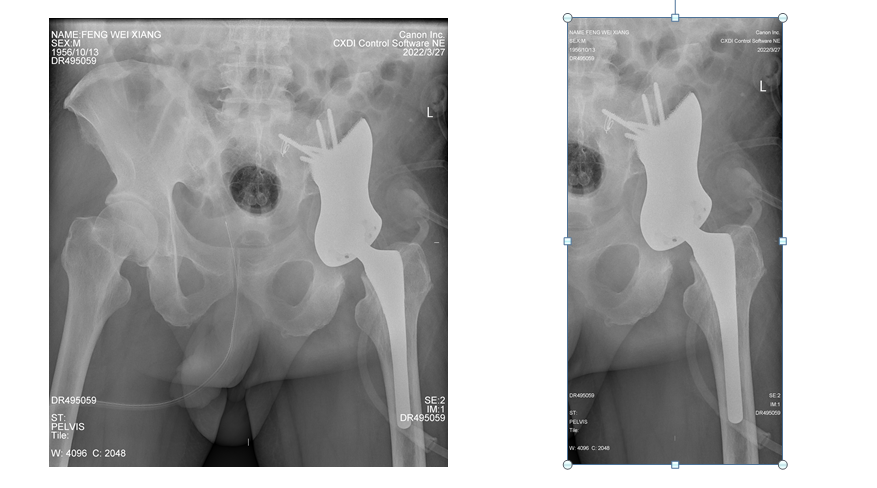

南医五院骨肿瘤规范化治疗团队与广东省人民医院骨肿瘤科团队组织讨论,为患者制定了术前3D打印个性化半骨盆假体及精准截骨导板(图2、3),术前介入栓塞骨肿瘤及周围的供血动脉围手术期准备下的骨盆切除髋关节功能重建手术。

图2:盆骨肿瘤切除范围及精准截骨导板

图3:定制3D打印个性化半骨盆置换髋假体

经过约6个小时,手术精准切除了髋臼区的肿瘤并重建了髋关节的功能(图4)。虽然出血量控制在正常范围,但手术为患者输血超2000ml,接近成年男子体内一半的血量,患者术后恢复良好(图5)。“非常感谢钟华主任团队,我自己上网查了很多资料,亲友也介绍钟华主任,我很放心,从疗效上看,我们的选择是正确的。”方先生说,“大剂量输血要与血站沟通做工作,这方面我相信南医五院的水平。”

图5:术后骨盆X光片复查示假体位置及固定正常